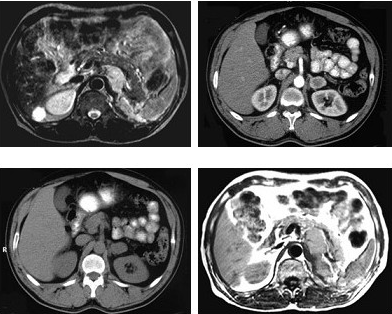

女,34岁,无意中发现血压高4个月就诊,行CT检查,如图所示,下列说法正确的是( )

A:CT示左侧肾上腺区可见一等密度块影,边界清楚

B:增强扫描,该病灶周边明显强化,中心处强化不明显

C:考虑为左肾上腺腺瘤

D:考虑为左肾上腺嗜铬细胞瘤

E:考虑为左肾上腺转移瘤